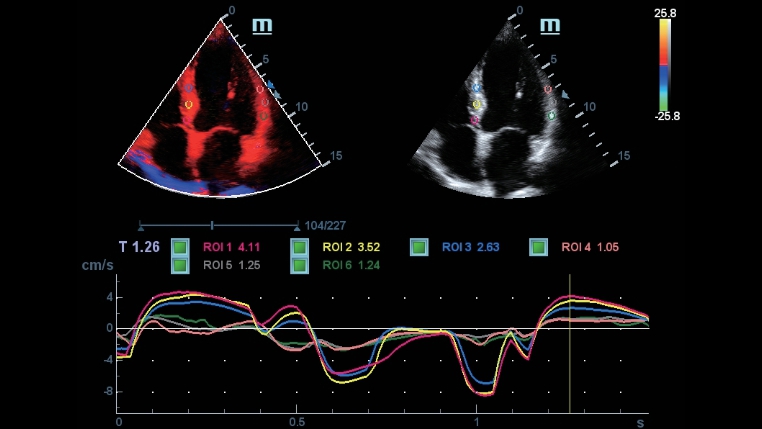

-TDI QA